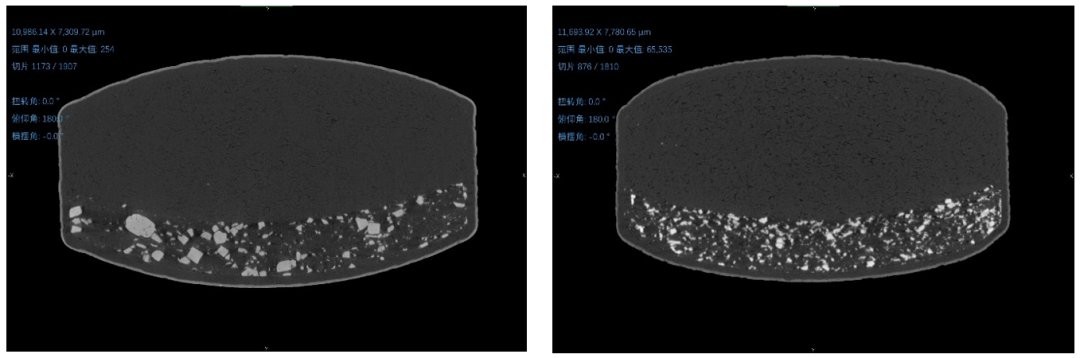

我國現(xiàn)代制藥業(yè)起步較晚,藥品生產(chǎn)以仿制為主。已批準上市的化學藥中,95%以上為仿制藥,涵蓋心腦血管系統(tǒng)、呼吸系統(tǒng)、抗腫瘤、抗感染等近30個治療領(lǐng)域,基本滿足公眾臨床用藥需求。 那什么是原研藥?什么是仿制藥呢?在這里先給大家做個簡單的普及。 原研藥主要指研發(fā)上市的藥品,原研藥已過了專利保護期的,其它企業(yè)可以進行仿制;仿制藥是與原研藥具有相同的活性成分、劑型、給藥途徑和治療作用的藥品。仿制藥僅復(fù)制原研藥的主要分子結(jié)構(gòu),省時省資省力,研發(fā)成本低,因此價格不高,可提高患者對藥品的可獲得性。 仿制藥一致性評價是指對已經(jīng)批準上市的仿制藥,按與原研藥品質(zhì)量和療效一致的原則,分期分批進行質(zhì)量一致性評價,就是仿制藥需在質(zhì)量與藥效上達到與原研藥一致的水平。開展仿制藥一致性評價,可以使仿制藥在質(zhì)量和療效上與原研藥一致 ,在臨床上可替代原研藥,這不僅可以節(jié)約醫(yī)療費用,同時也可提升我國的仿制藥質(zhì)量和制藥行業(yè)的整體發(fā)展水平,保證公眾用藥安全有效。 只有當要求評測的所有數(shù)據(jù)全部通過一致性的標準后,該仿制藥產(chǎn)品才有資格申請 “一致性評價” 的批準。(摘自福建省醫(yī)療保障局網(wǎng)站) 雖然仿制藥必須與原研藥具有一樣的藥物API、劑量、給藥途徑和劑型,且必須符合藥品質(zhì)量標準(活性成分含量,藥品純度等),但由于非活性成分方面(比如幫助藥片成型而添加的淀粉、蔗糖等輔料),仿制藥不需要完全與原研藥一致,那這些些許的不一致是否會對藥物的釋放,在速率、時長等方面帶來差異呢? 就以硝苯地平為例,是所有的品牌的硝苯地平都可以做到同樣的釋放速率嗎?或者說釋放速率會有多大的差異呢?如前文提到的鄧老師作為一位嚴謹?shù)目茖W家,想在了我們的前面。我們的疑問在鄧老師的另一個對比視頻里得到了解答。在這個視頻里我們看到不同品牌的仿制藥在藥物釋放的速度、時長及釋出藥物顆粒的粗細程度皆不完全一致,這很有可能會對患者的用藥效果產(chǎn)生影響,比如降壓的效果及持續(xù)的時長等方面。 那造成這些差異的原因和因素會有很多種可能,我們也在鄧老師的指點之下,嘗試用三維X射線顯微成像(3D XRM)揭開其中的些許可能性。 小嘉將之前購買的拜耳公司拜新同和其他品牌的硝苯地平控釋片放入布魯克的SkyScan 1273型號的三維X射線顯微成像系統(tǒng),在條件參數(shù)一致的情況下進行掃描成像,觀察對比兩者的結(jié)構(gòu),試圖能找出一些差異的蛛絲馬跡。 掃描完成后,我們對原始的數(shù)據(jù)進行了重構(gòu),并進行了三維可視化的渲染。我們對兩款藥物的三維空間結(jié)構(gòu)形態(tài),推動劑的占比,孔隙率等多個維度進行了對比,獲得了如下的圖片和數(shù)據(jù)信息: ① 三維空間結(jié)構(gòu)形態(tài) 左圖為原研藥,右圖為仿制藥 ② 推動劑結(jié)構(gòu)形態(tài) 左圖為原研藥,右圖為仿制藥。顏色為隨機染色 ③ 整體孔隙率及推動劑占比數(shù)據(jù)的定量計算 左圖為原研藥,右圖為仿制藥。 從上面的圖片、動畫以及數(shù)據(jù)我們可以得到如下一些信息: 1、 原研藥的整體孔隙率是大于仿制藥的 (2.79% Vs 1.70%) 2、兩款藥的孔隙分布都是隨著孔徑增大而減少的趨勢,但仿制藥的孔徑分布中位數(shù)要明顯小于原研藥 3、原研藥的推動劑整體占比也是大于仿制藥的 (5.11% Vs 3.60%) 4、仿制藥的推動劑顆粒均勻度好過于原研藥 至于以上這些因素是否是造成如鄧老師視頻里這些藥物呈現(xiàn)釋放差異的主要或根本原因,小嘉在這里不敢妄下定論,畢竟布魯克的3D XRM設(shè)備提供的是圖片、動畫和數(shù)據(jù)之類的旁證。至于更根本的原因,還是需要如鄧老師他們這樣的科學家結(jié)合觀察到的實際情況以及我們這類設(shè)備提供的旁證來綜合考量,再來進行原因的判斷。 原研藥的研發(fā)是一個高成本、長周期的工作,需經(jīng)過對成千上萬種化合物層層篩選和嚴格的臨床試驗才能得以獲準上市,平均需要花費15年左右的研發(fā)時間和數(shù)億元。但這也往往也能代表一個國家的醫(yī)藥工業(yè)和研發(fā)實力的水平。 希望我國的原研藥研發(fā)可以蒸蒸日上!小嘉攜布魯克的3D XRM也希望能在這過程中做出一點微薄的貢獻和努力,成為科學家們的稱手工具。 相關(guān)產(chǎn)品 更多